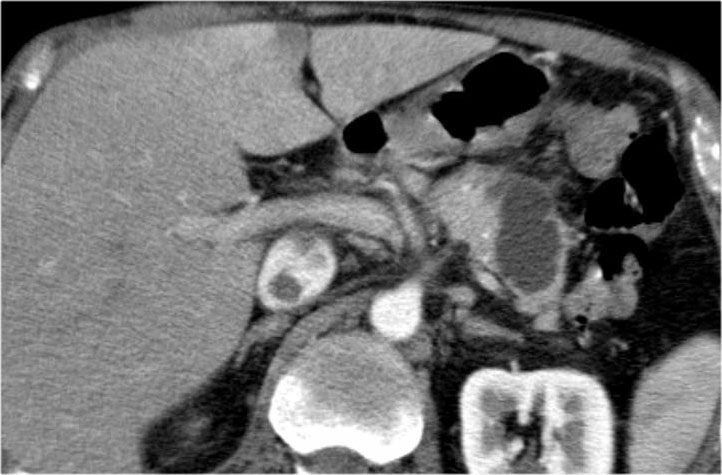

Bệnh nhân này bị viêm tụy mạn tính.

Lưu ý các vôi hóa ở đầu tụy (mũi tên cong).

Có nhiều nang giả tụy lan dài vào tận trung thất, gây chèn ép tim (mũi tên đỏ).